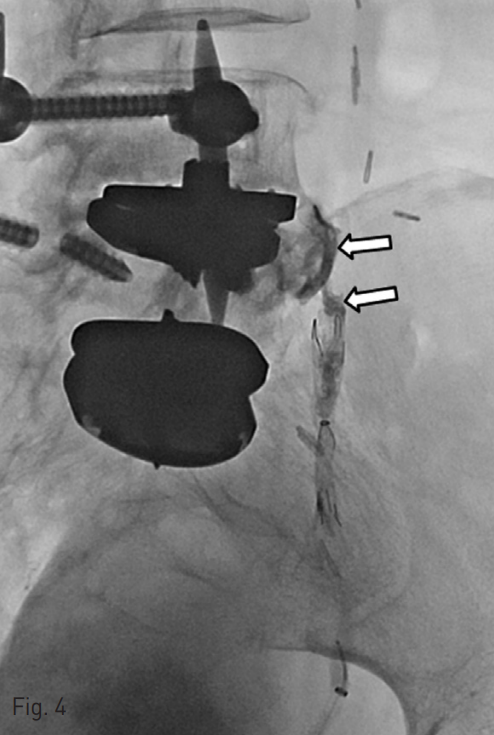

Then, we used N-butyl cyanoacrylate glue (n-BCA, 1 : 3, total 3cc) material to embolize the fistulous tract via microcatheter in left CIA occlusion site pseudoaneurysm (Fig. 4). The postembolization angiogram confirmed the obliteration of the fistulous tract (Fig. 5).

Fig. 4

The fistulous tract between the left CIA occlusion site pseudoaneurysm and ureteric stump was embolized using N-BCA (arrows).